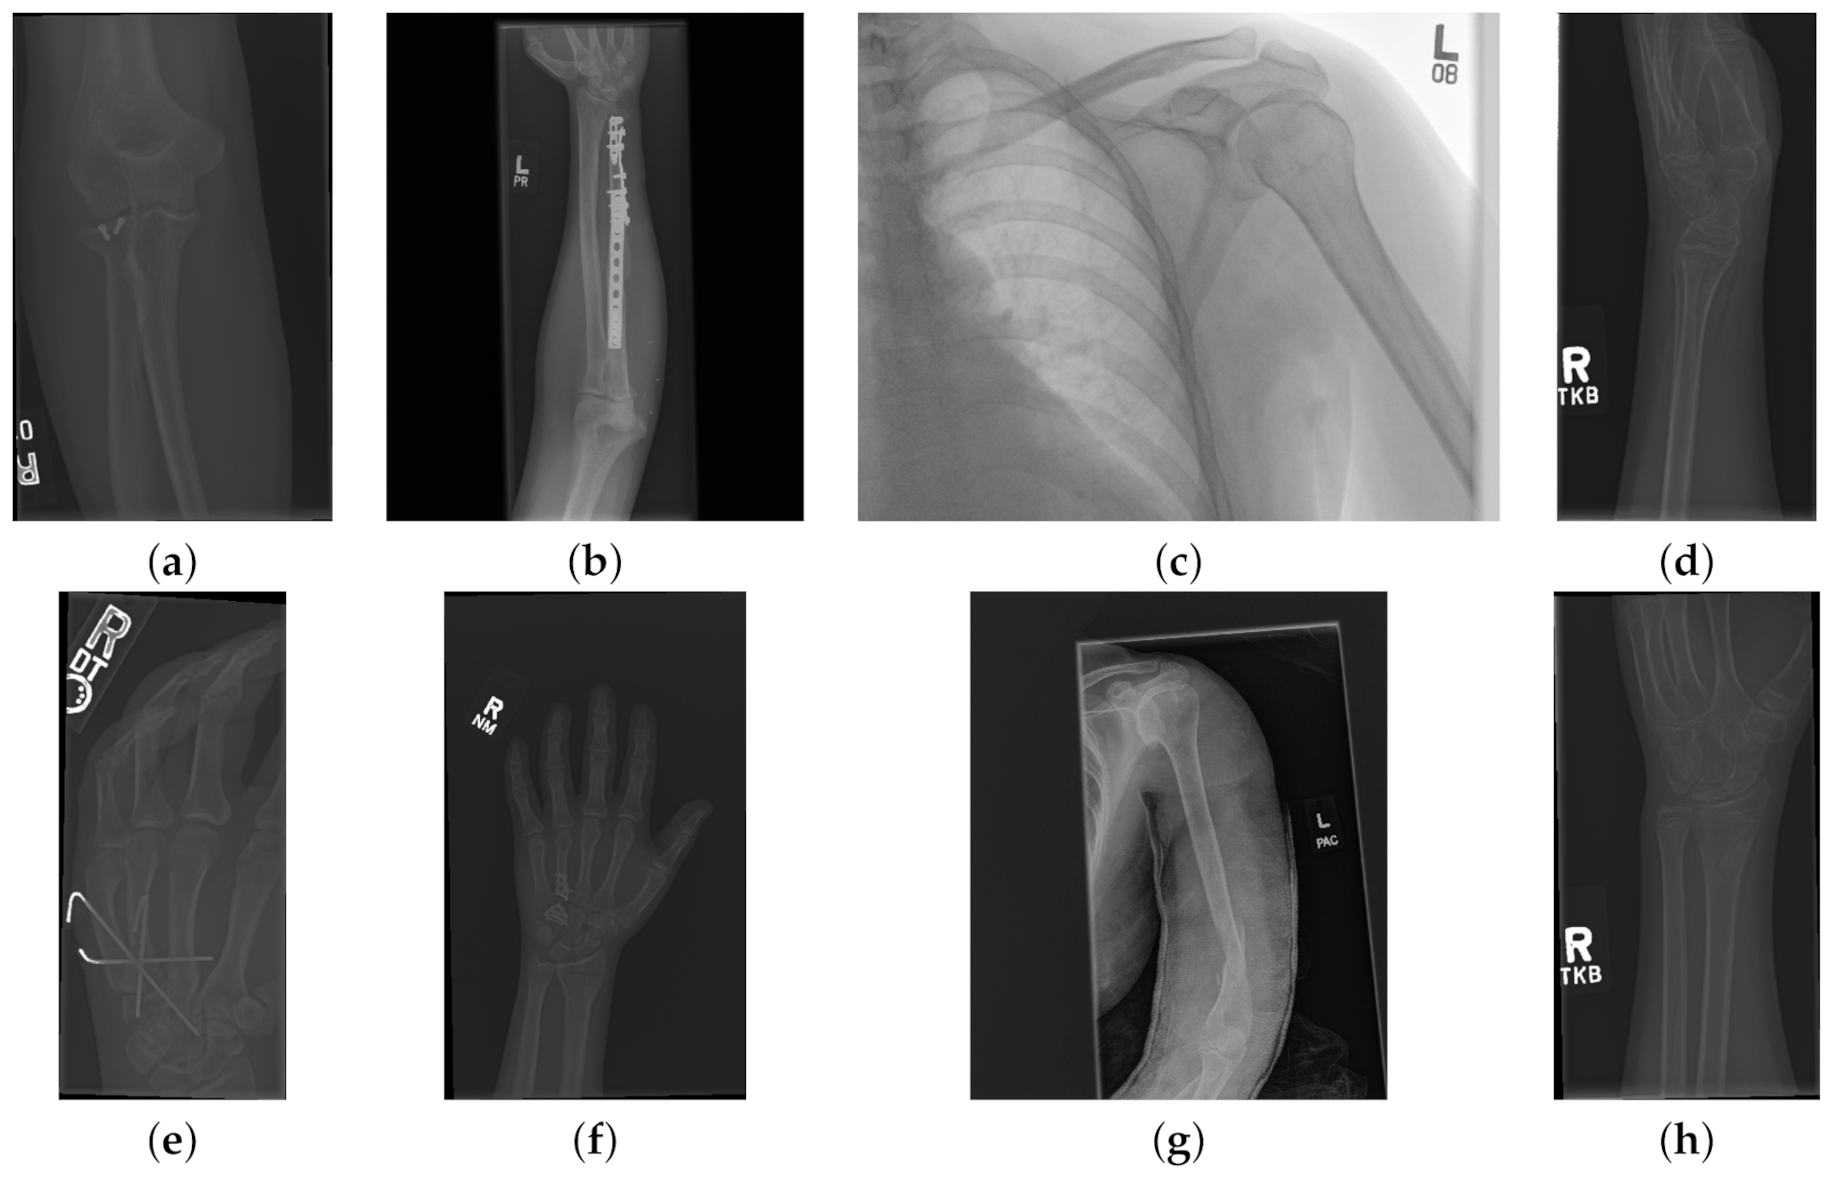

The data used to compare the 11 CNNs was obtained from the public dataset MUsculoskeletal RAdiographs (MURA) from a competition organised by researchers from Stanford University [59]. The dataset has been manually labelled by board-certified radiologists between 2001 and 2012. The studies (n = 14,656) are divided into training (n = 13,457), and validation (n = 1199). Furthermore, the studies have been allocated in groups called abnormal (i.e., those radiographs that contained fractured bones, foreign bodies such as implants, wires or screws, etc.) ( n = 5715 ) or normal ( n = 8941 ). Representative normal cases are illustrated in Figure 1 and abnormal cases in Figure 2. The distribution per anatomical region is shown in Table 1. In this paper, the subset of the wrists was selected. The cases of normal and abnormal wrist radiographs is presented in Table 2. Notice that these were subdivided into four studies.

Figure 1. Eight examples of radiographs without abnormalities (considered negative) of the Musculoskeletal Radiographs (MURA) dataset [59]. (a) Elbow, (b) Forearm, (c) Shoulder, (d) Wrist (lateral view), (d) Lateral view of Wrist, (e) Finger, (f) Hand, (g) Humerus, (h) Wrist. It should be noted the variability of the images in terms of dimensions, quality, contrast and the large number of labels (i.e., R for right and L for left), which appear in various locations.